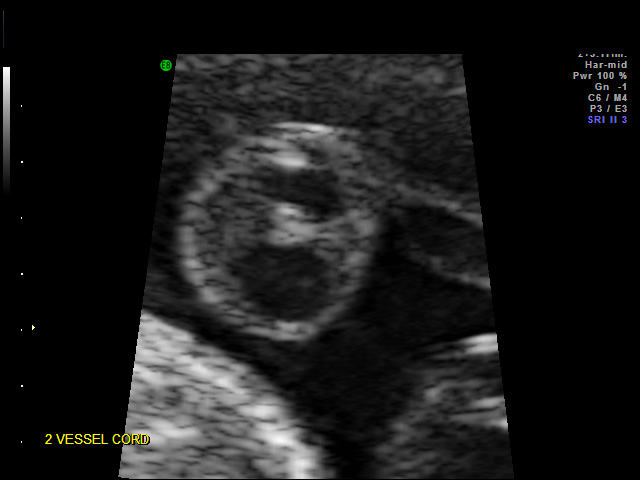

3. Color flow with

absent right artery

Transverse with only

one umbilical artery

seen instead of 2